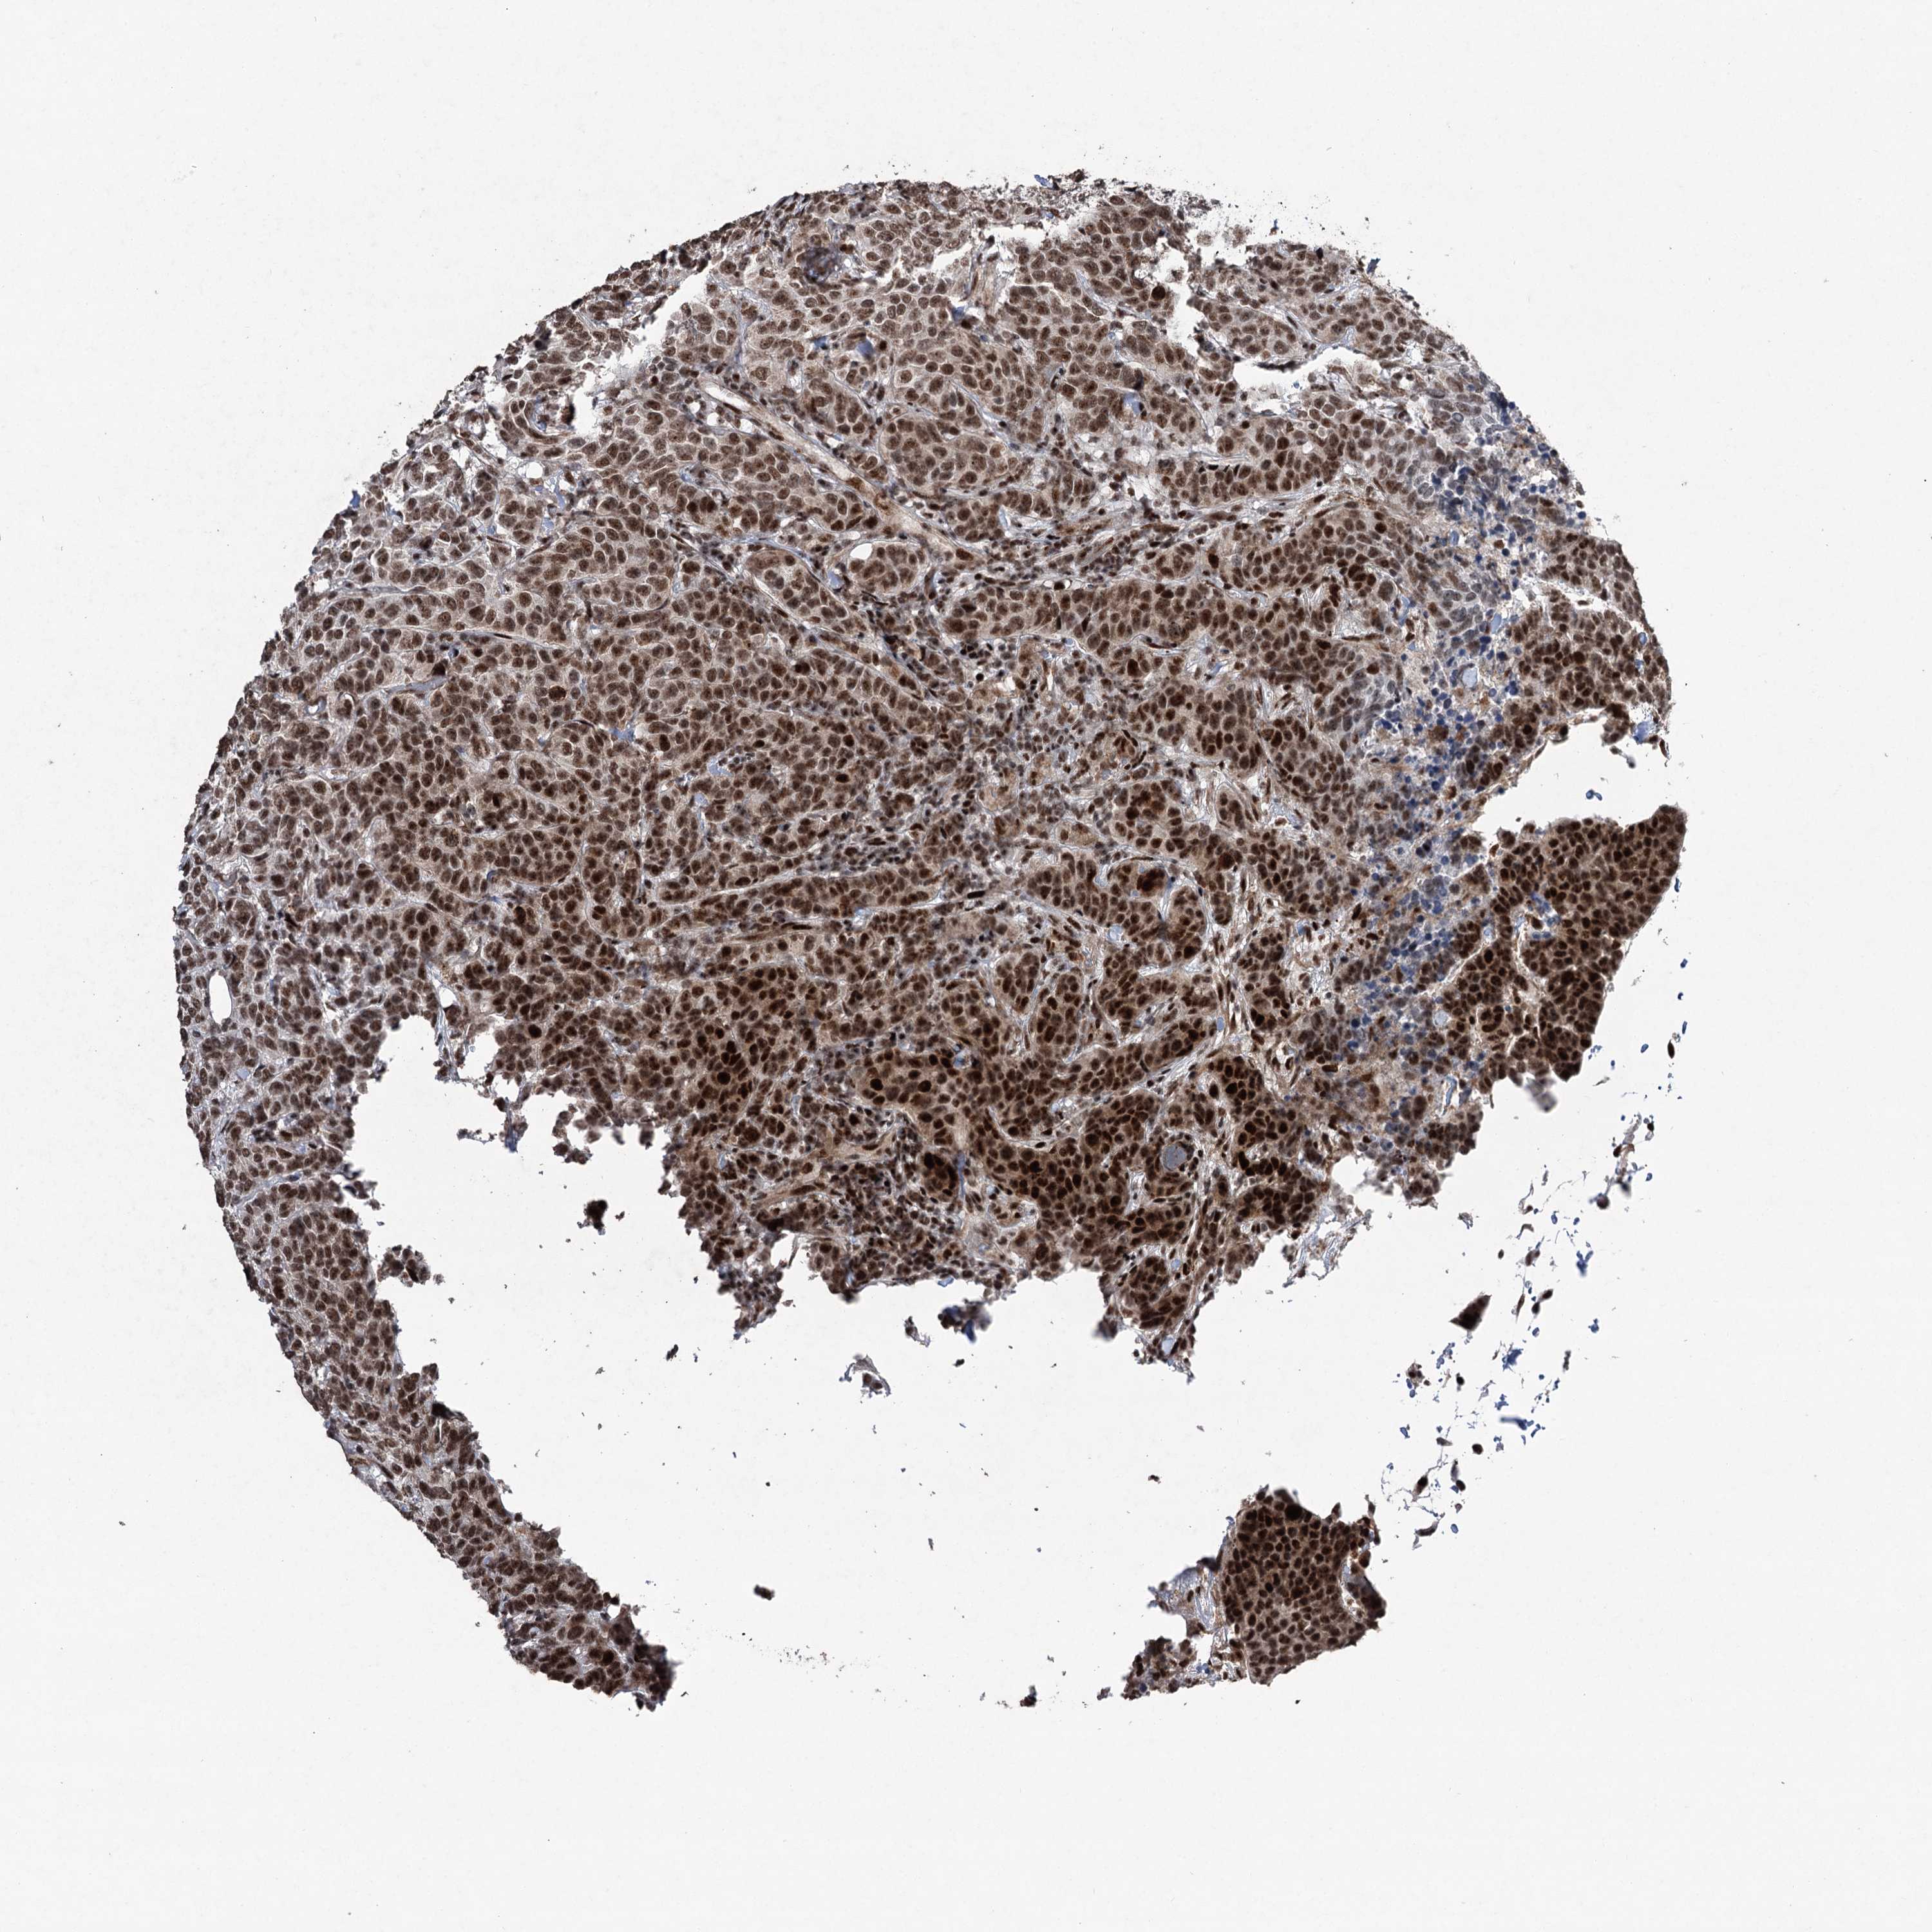

CANCER BREAST CANCER Show tissue menu

BRCA TCGA BRCA VALIDATION PROTEIN EXPRESSION